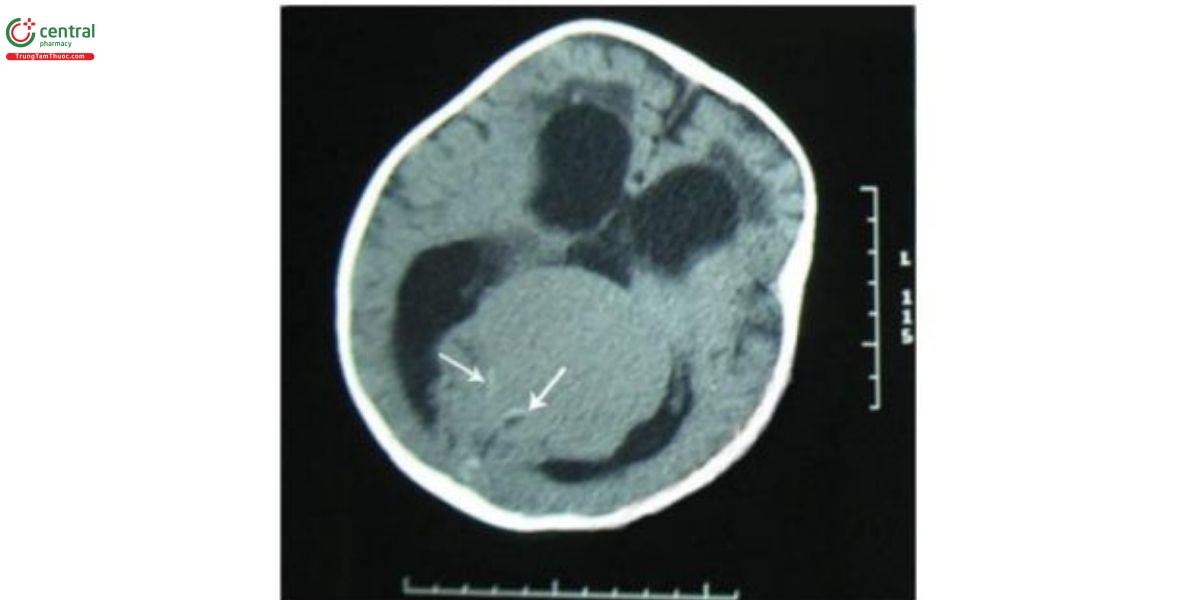

Huyết khối tự phát trong VGAM là hiểm và cơ chế vẫn chưa được hiểu đầy đủ. Có nhiều yếu tố được mô tả, bao gồm thay đổi huyết động (dòng chảy chậm, tăng áp lực hoặc nhiều loạn), co mạch, tăng sinh mạch, và các thay đổi xơ vữa thoái triển trong mạch máu. Dẫn lưu thất và việc sử dụng thuốc cản quang trong chụp mạch cũng được cho là có liên quan đến huyết khối trong VGAM. Các phương pháp hình ảnh có thể mô tả rõ các đặc điểm của huyết khối. Trên CT, có thể thấy tin hiệu không đồng nhất, đôi khi kèm theo vôi hóa. CT cản quang cho thấy huyết khối trung tâm và dòng máu tuần hoàn quanh thành túi, được gọi là "target sign", MRI của VGAM có huyết khối cho thấy methemoglobin ngoại bào ở phần trung tâm và hemosiderin ở phần ngoại vi của tôn thương.